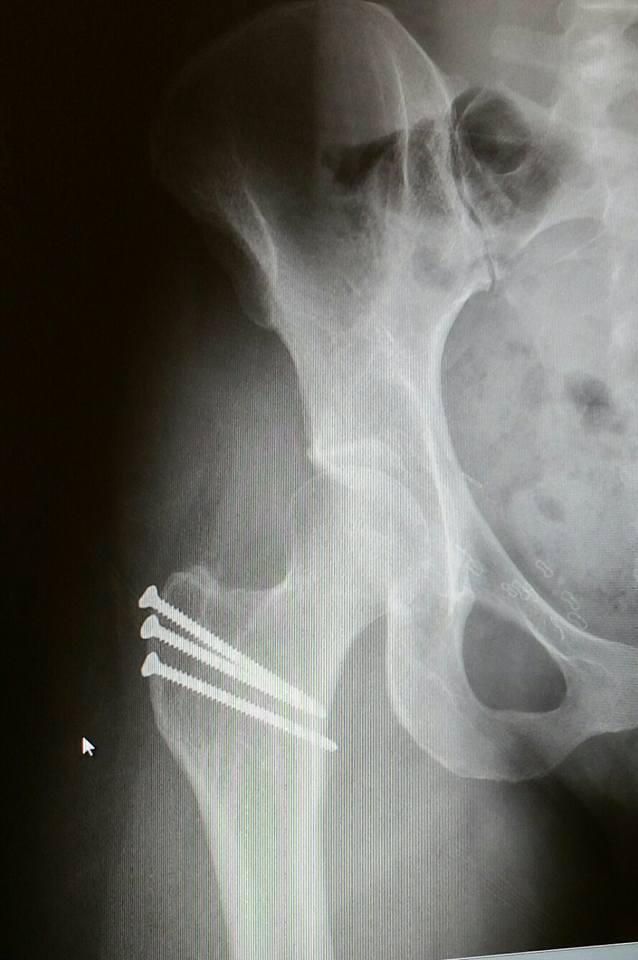

All I wanted was a better quality of life without pain. I was given that chance when I met Dr. Ernest Sink. It was not until I was evaluated by Dr. Sink at age 28, that I would finally get answers. After extensive testing, I was diagnosed with a condition called hip dysplasia. Hip dysplasia is a condition in which the hip socket doesn't fully cover the ball portion of the upper thighbone.

In July 2016, I underwent a femoral osteotomy of my right hip. I knew that it would be a long road to recovery and I was ready. I am now almost two years post surgery and I can say that it was the best decision of my life! The pain and discomfort I felt for so many years in my right hip is gone and I am so grateful for Dr. Sink for making this possible.